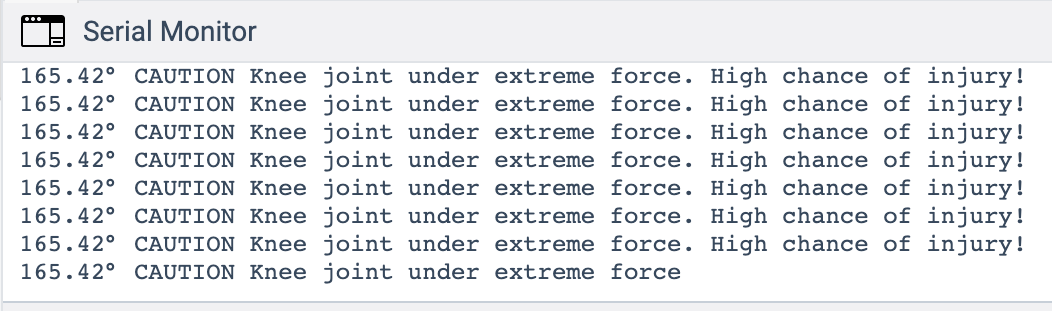

_ PROJECTS

Water Ejection System (iOS)